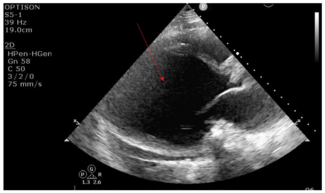

This case visually demonstrates the effect of LV unloading in a 30-year-old male, with a history of coronavirus disease 2019 (COVID-19) myocarditis. The patient developed COVID-19 and subsequently developed nonischemic cardiomyopathy with an...